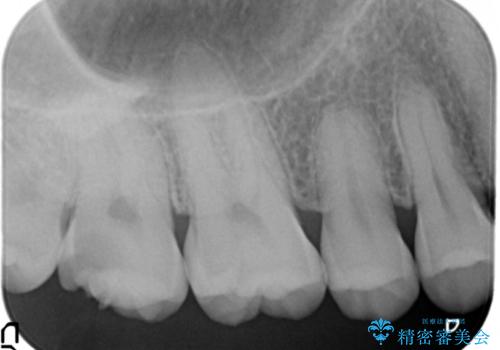

精査したところ、神経近くに及ぶ大きなう蝕を認めました。

神経をとらずに済むよう丁寧にう蝕を除去したのち、セラミックインレーで修復しました。

う蝕リスク軽減のため親知らずの抜歯をお勧めしましたが、ご希望されませんでした。